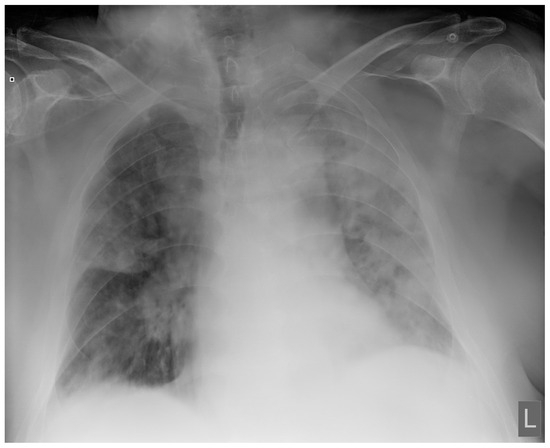

Laboratory findings were mostly normal; C-reactive protein was elevated in all patients with a mean value of 129.7 ± 80.74 mg/L. The arterial blood gas analysis showed hypoxemic respiratory failure. Chest X-rays in all patients showed bilateral inhomogeneous infiltrates (Figure 1 and Figure 2). In three patients, CTPA was performed, which ruled out pulmonary thromboembolism, but ground-glass opacifications with consolidation of the lung parenchyma were described in all of them (Figure 3 and Figure 4) [15].

Figure 1. Chest X-ray upon admittance: patient 5. Bilateral inhomogenous infiltrates typical for COVID-19 pneumonia (the “L” orientation marker indicates the left side).